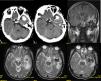

Se presenta un caso de aneurisma gigante no traumático de la arteria meníngea media en un paciente de 59años con antecedentes de trasplante hepático, cirrosis hepática y hepatocarcinoma, enfermedad renal crónica, HTA y bronquitis crónica que ingresó por presentar crisis tónico-clónica. La TC y la RM mostraron una lesión sugestiva de metástasis sin descartar un tumor de tipo glial. Fue intervenido mediante una craneotomía FT izquierda. Durante la cirugía se produjo una hemorragia arterial. La muestra histológica orientó hacia un origen aneurismático que se confirmó con ARM y angiografía. Una segunda intervención permitió la extirpación de un aneurisma gigante de la arteria meníngea media parcialmente trombosado. Los aneurismas de la arteria meníngea media son raros y en general presentan un antecedente traumático. No se ha encontrado en la literatura médica ningún caso de aneurisma gigante.

A case of a non-traumatic giant aneurysm of the middle meningeal artery is presented in a 59-year-old patient with a history of liver transplantation, liver cirrhosis and hepatocarcinoma, chronic renal disease, hypertension and chronic bronchitis who presented with tonic-clonic seizures. CT and MRI showed a lesion suggestive of metastasis without ruling out a glial type tumor. He was operated through a left FT craniotomy. During the surgery there was an arterial hemorrhage. The histological sample oriented toward an aneurysmal origin that was confirmed with ARM and angiography. A second intervention allowed the removal of a giant middle meningeal aneurysm partially thrombosed. Aneurysms of the middle meningeal artery are rare and generally present a traumatic history. No case of giant aneurysm has been found in the medical literature.